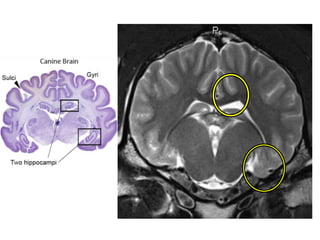

Hipocampo

• Se ubica entro de los lóbulos temporales, junto a

la amígdala.

• En el se incluyen: Corteza perirrinal, entorrinal y

paraphipocámpica.

• Actúa como indexador de memoria mediante el

envío de memorias a la parte apropiada del

hemisferio cerebral para el almacenamiento a

largo plazo y recuperar cuando sea necesario.

• Función: Consolidación de nuevos recuerdos,

respuestas emocionales y orientación espacial.

Sistema límbico canino